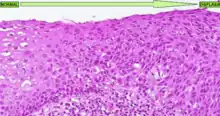

La forma más conocida de displasia es la displasia cervical, bastante común en las lesiones precursoras del cáncer de cuello de útero. Es un tipo de displasia que tiene como causa etiológica el papillomavirus humano y que afecta al cérvix uterino de las mujeres. En este tipo de displasia se observa una diferenciación muy clara del tejido cervical dañado respecto al tejido sano (ver imagen adjunta). En esta enfermedad hay tres grados de displasia diferentes:

Cuando se alcanza el nivel grave puede ser llamado carcinoma "in situ", que es una forma temprana de tumor).